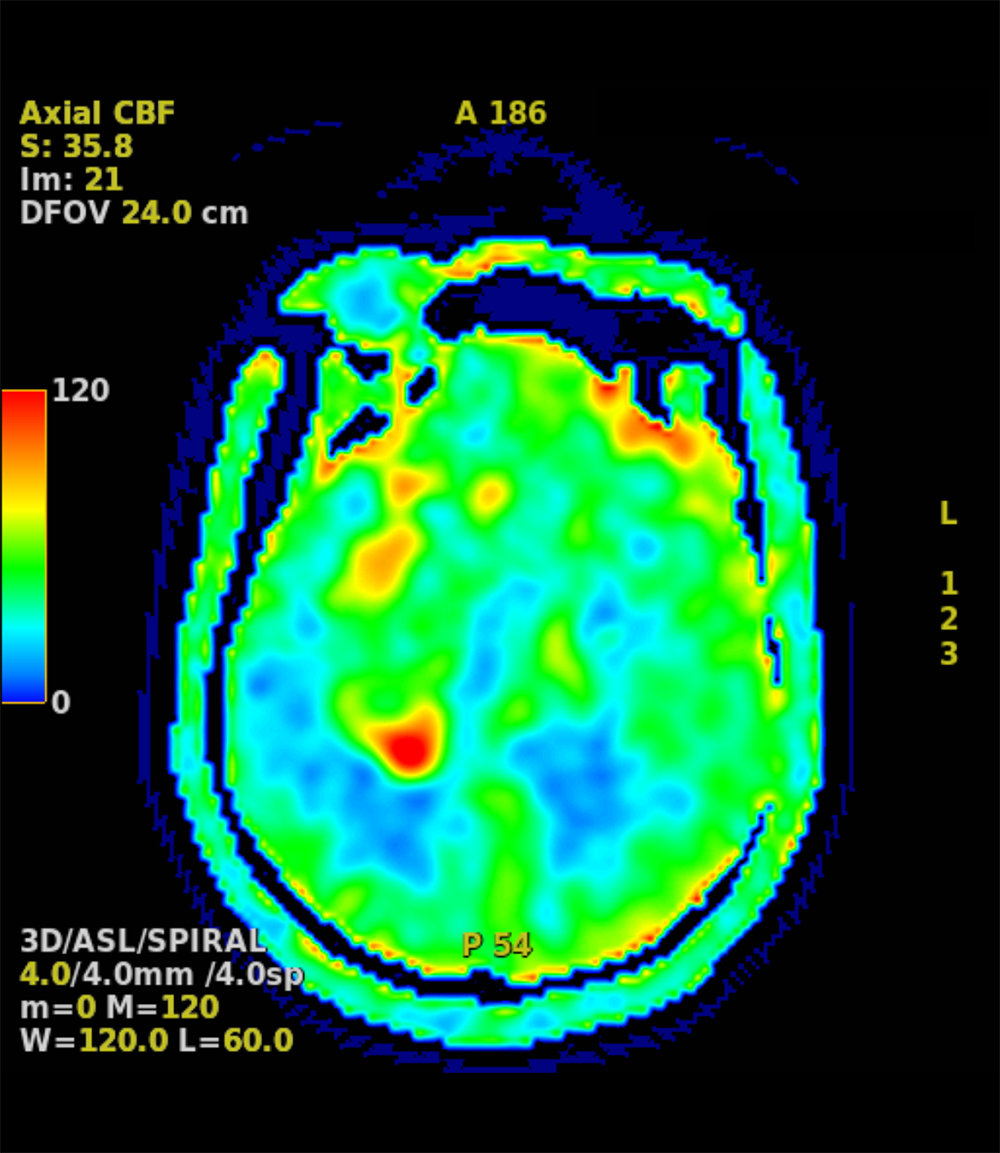

| 3D ASL PLD=2025 | 3D ASL | 1:47 | 4843 | 10.5 | 2025 | 155 | ー | ー | ー | ー | 2 |

| 3D ASL PLD=2025 | 240 | ー | ー | ー | 4 | 0 | 36 |

2週間前からの頭痛にて前医を受診し、CTで頭蓋内腫瘤や脳浮腫を認めたため、当院へ救急搬送された。当院で施行された造影MRIでは右側頭葉~前頭葉に約7.5×4cmの辺縁不整な腫瘤を認め、膠芽腫が疑われた。その後手術が施行され膠芽腫の診断に至り、手術後は化学放射線治療が施行された。

受診当日に施行されたCT/MRIにて偶発的に腫瘤が発見された。非造影のCTやT1強調画像、T2強調画像、拡散強調画像などでは腫瘤の存在や輪郭が不明瞭であることも多く、本症例のように造影を行うことで腫瘤の詳細な評価が可能となる。一般的には転移性脳腫瘍や脳膿瘍などが鑑別となり、その他のシーケンスや体幹部の所見、臨床データなどとも併せて診断を行うことが重要である。